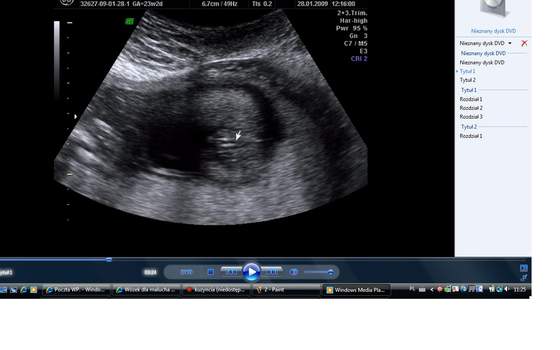

)...no nic najważniejsze...weszłam do gabinetu i od razu zaczęłam słyszeć bijące serduszko a na wielkim monitorze widziałam dzidzię (taką jak ma yoohoosek w sygnaturze dosłownie w takim formacie